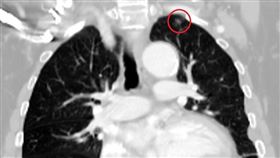

運動女才50歲罹肺腺癌 日常1習慣藏危機

桃園一名50歲的李小姐經營機車行,並擔任消防局義消多...